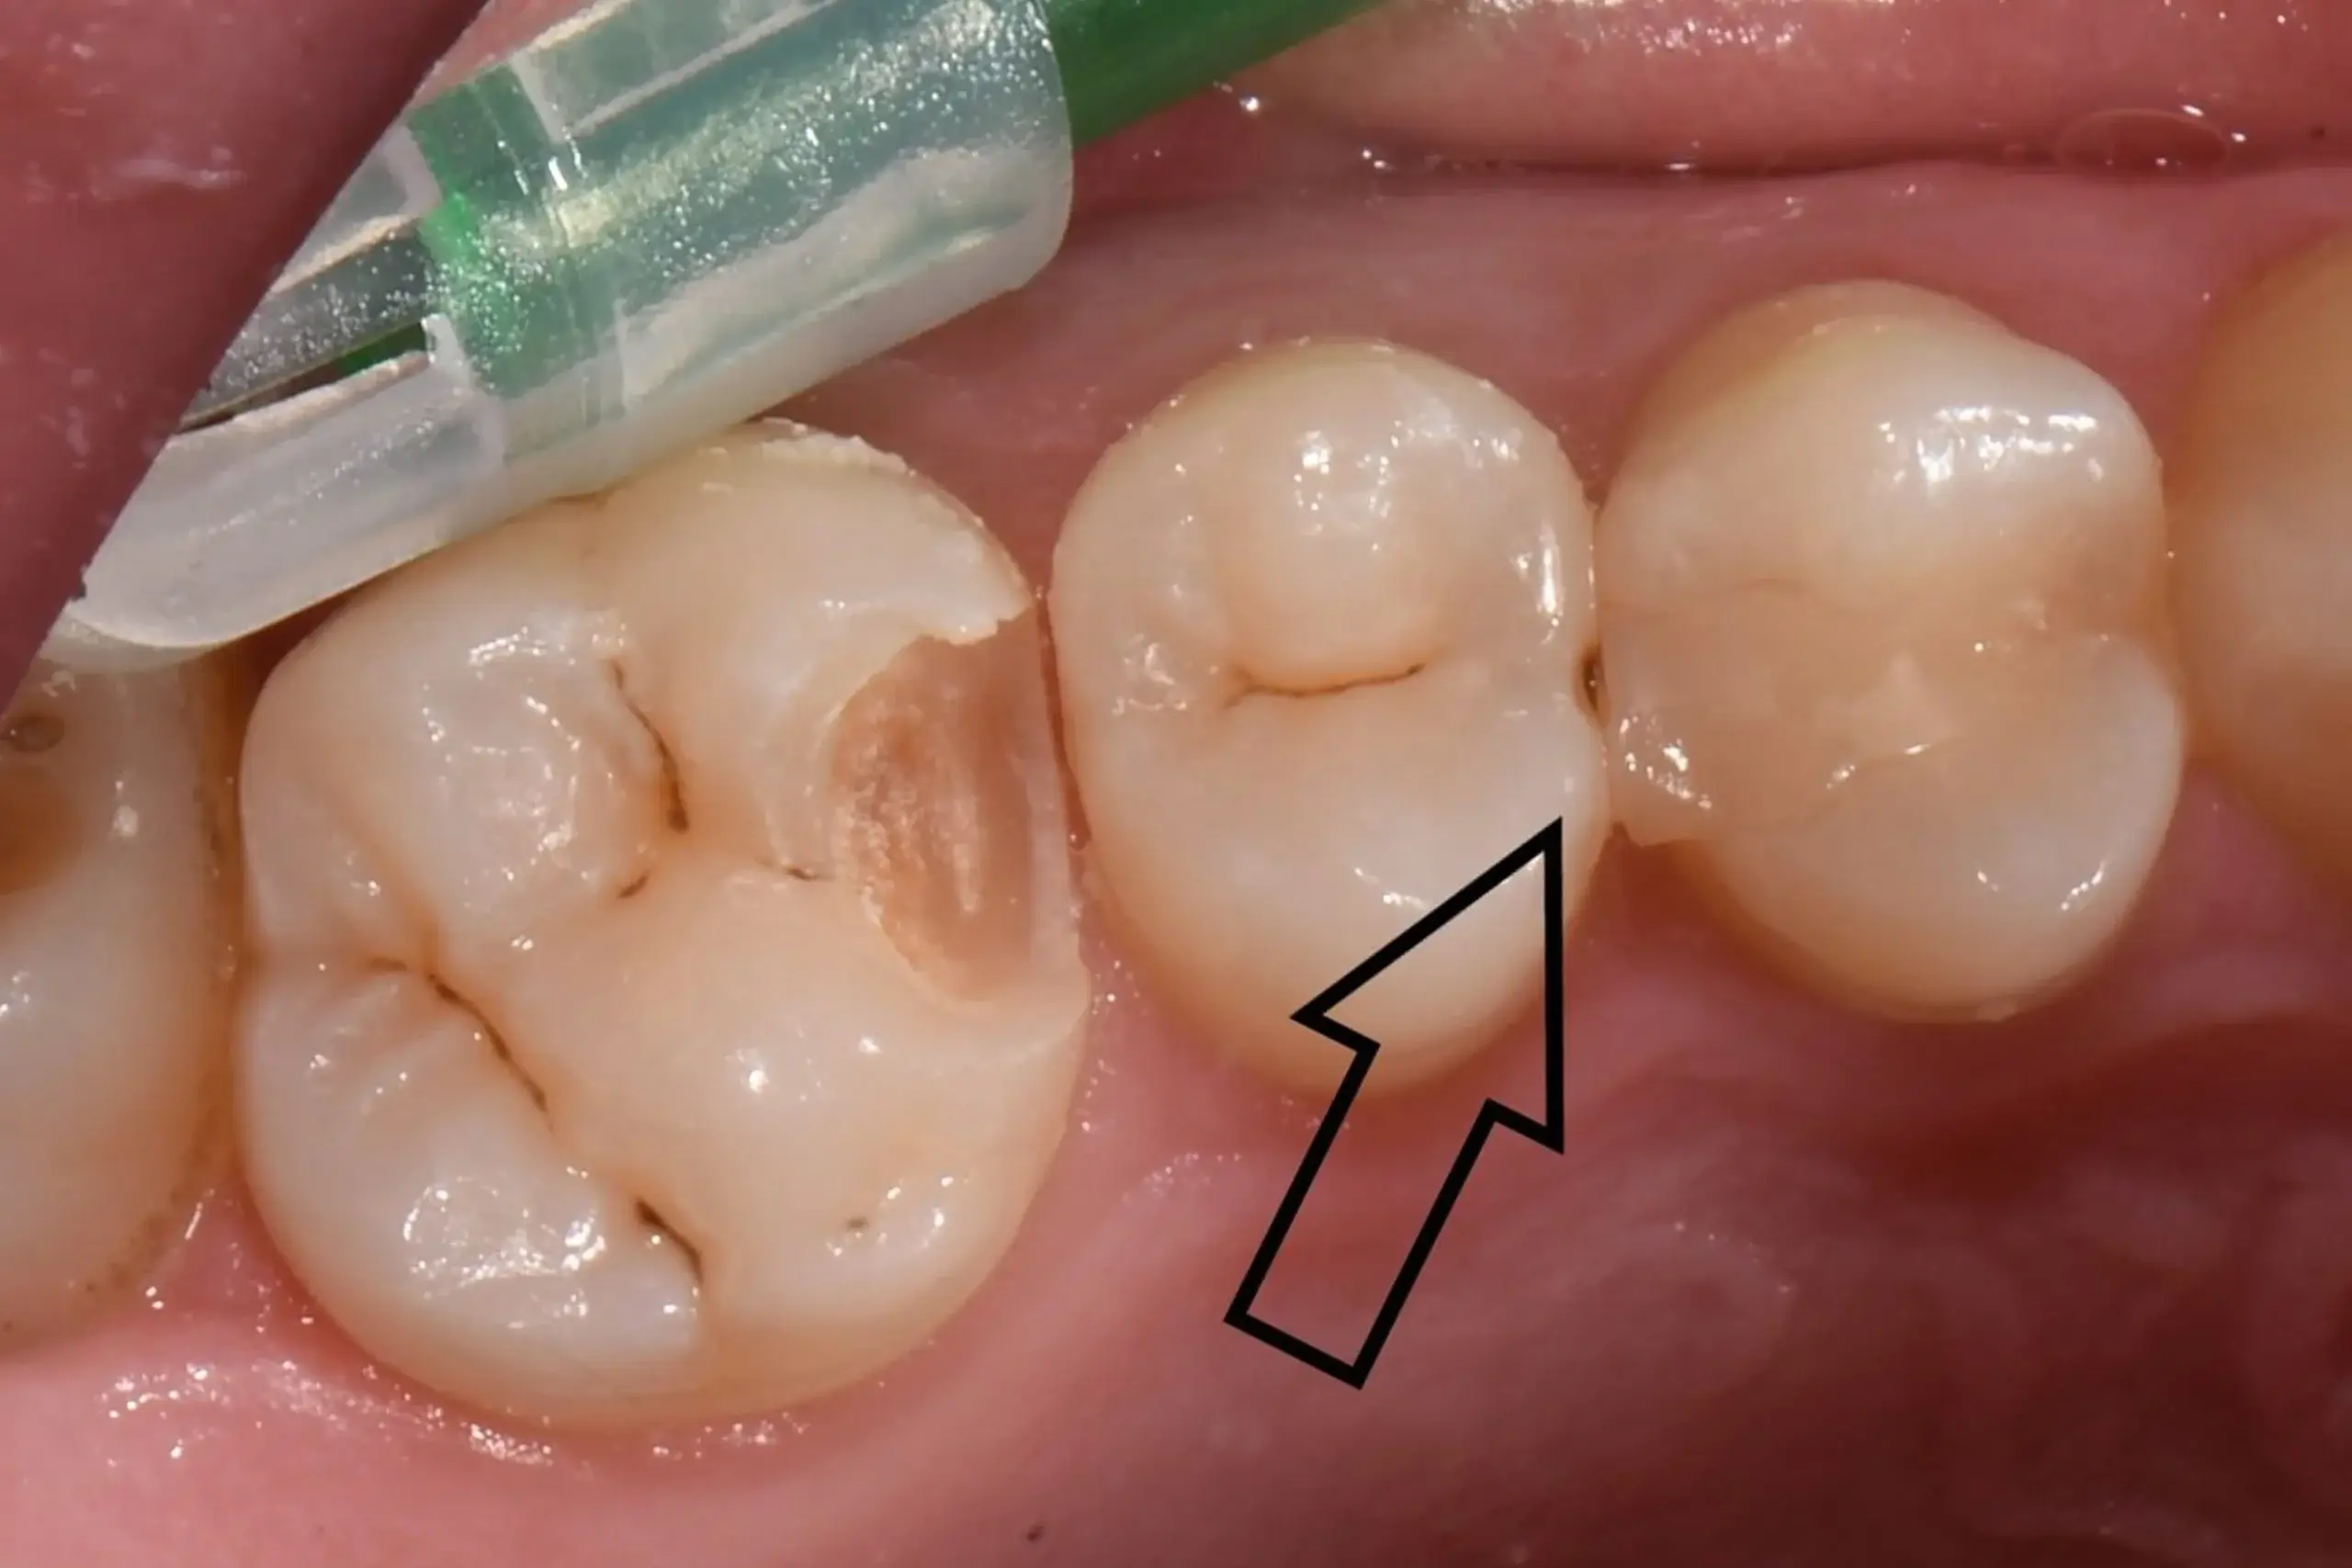

Wir legen besonderen Wert auf eine hochwertige Verarbeitung, denn schlussendlich darf man die handwerkliche Komponente der Zahnmedizin nicht außer acht lassen - was zu erheblichen Qualitätsunterschieden führt, die Sie hier auf einer Makro-Fotoaufnahme sehen können.

Ich gebe mir größte Mühe, dass die Composite Füllung sowohl funktionell wie auch von der Ästhetik her der Vervollständigung Ihres natürlichen Zahnes entspricht.